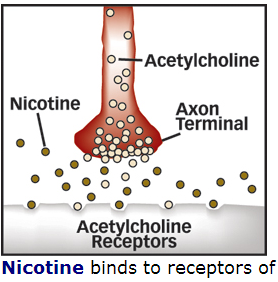

55 brain levels of thought